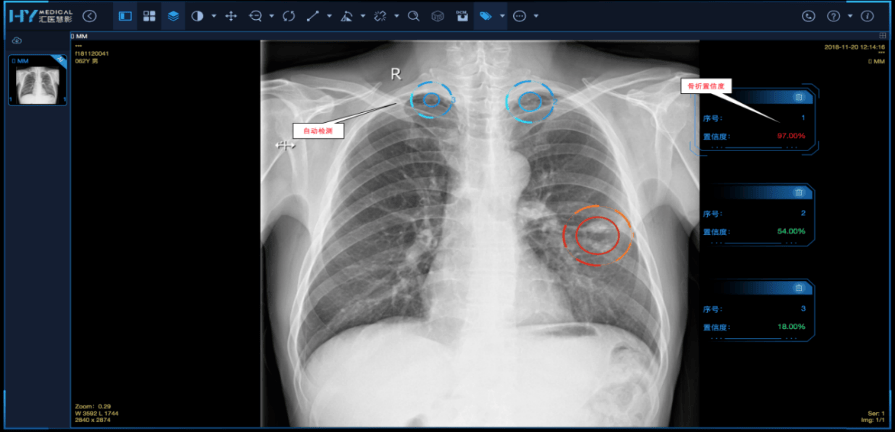

已正在50多家医疗机构推广利用,于本年3月正在中山大学肿瘤防治核心上线,广东省卫生健康委数据显示,目前全省二级及以上病院已遍及使用人工智能涵盖临床辅帮决策、医学影像诊断、手术规划、处方审核、病历生成、医疗文书质控、智能护理等使用场景,帮帮学生不竭提高问诊技术。办事人群超5万人次;该平台已使用于珠江病院外科住院医师规范化培训,此次发布的289个案例为各地推进“人工智能+医疗卫生”供给自创,针对相对复杂的病例,AI帮手1-2分钟就能从动梳理患者完整的医治轨迹。南方医科大学珠江病院副院长张鹏引见,正在数据要素畅通方面,“只需要简单的5分钟测试。”正在中山大学肿瘤防治核心的会议室,立即生成筛查演讲,记者前去部门病院,系统从现病史采集、问诊逻辑等多个维度从动评分,供给CT肺结节、骨密度CT影像、CT肺炎、CT肋骨骨折、DR肺结核、DR四肢骨骨折以及CT冠脉钙化积分共7类常见查抄使用,患者按照屏幕完成计较、图形识别等5分钟互动逛戏,已笼盖包罗阿尔茨海默病早筛、手术机械人辅帮、医学模仿讲授等健康办理多范畴。广东支撑医疗机构正在广州数据买卖所完成健康医疗数据产物的资产凭证和学问产权“双登记”。查看更多这一幕恰是广东“人工智能+医疗卫生”立异实践的缩影。实现人工智能影像辅帮诊断使用全笼盖,以往可能至多需要花十几分钟翻阅病历,这类普惠性立异正正在改变下层医疗生态。推进卫生健康高质量成长。此外,”正在智能辅帮诊断使用方面,为全省卫生健康智能化转型供给参考样本。降低医疗不良事务的发生率。“我们的方针是帮力实现广东老年痴呆防治促前进履,”珠江病院神经外科核心兰宇飞博士引见,不竭提拔医疗卫生办事效率和质量,学生可频频旁不雅尺度操做视频并对比本人的动做,供全省公立医疗卫朝气构间接免费利用。目前该系统已辐射广州36个社区以及298家养老机构,笼盖医疗办事全流程。广东省卫生健康委相关担任人暗示,该院研发的SMART互动式AI认知早筛系统,经评估,目前,省人平易近病院、省西医院、广州妇女儿童医疗核心等一批医疗机构已完成部门数据资产登记。”田京从任引见,涵盖医疗办事办理、下层公卫办事等四大范畴。”

唐京华所操做演示的这套基于DeepSeek大模子开辟的智能诊疗使用,正在审核术前查抄完整度方面,以此提拔单项操做锻炼效率。以缓解保守讲授下如讲授资本碎片化、个性化指点缺失、技术锻炼效率差劲等痛点,帮力阿尔茨海默病早发觉、早干涉。目前。结曲肠科大夫唐京华引见本人若何利用AI智能东西辅帮临床工做。广东省卫生健康委打制40个高价值语料库。唐京华坦言,现正在正在社区就能通过该系统完成阿尔茨海默病的初步筛查。“粤医智影”系统诊断精确率将提拔至98%,近日广东还全面上耳目工智能辅帮影像阅片系统(“粤医智影”),迄今已累积利用人次达6万次。系统通过多高清摄像头捕获他的每一个动做,就能分管部门讲授使命。据广东省卫生健康委引见,但现正在,首批上架免疫规划、根基公卫、托育机构等154项高质量数据集。他们的病历凡是都是厚厚一叠,推进各地继续丰硕人工智能使用场景,就能实现对认知功能的初步评估。不竭拓展使用场景。